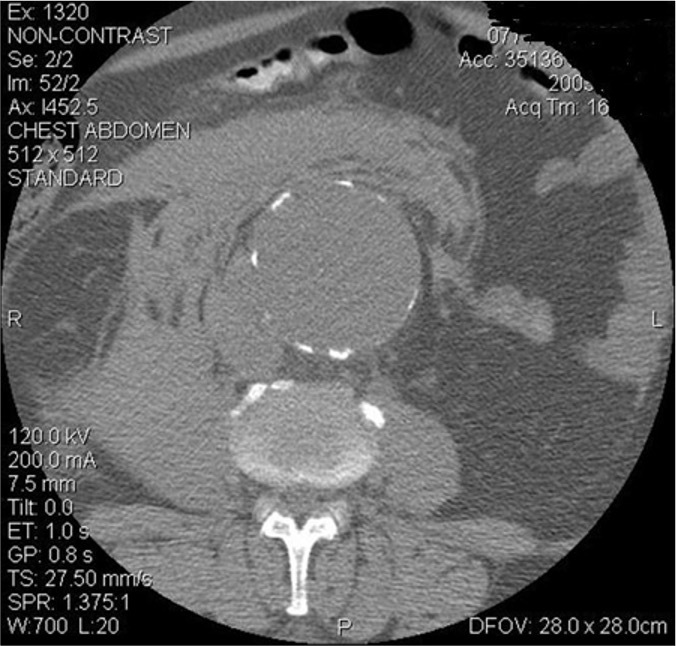

Ruptured AAA

AAA